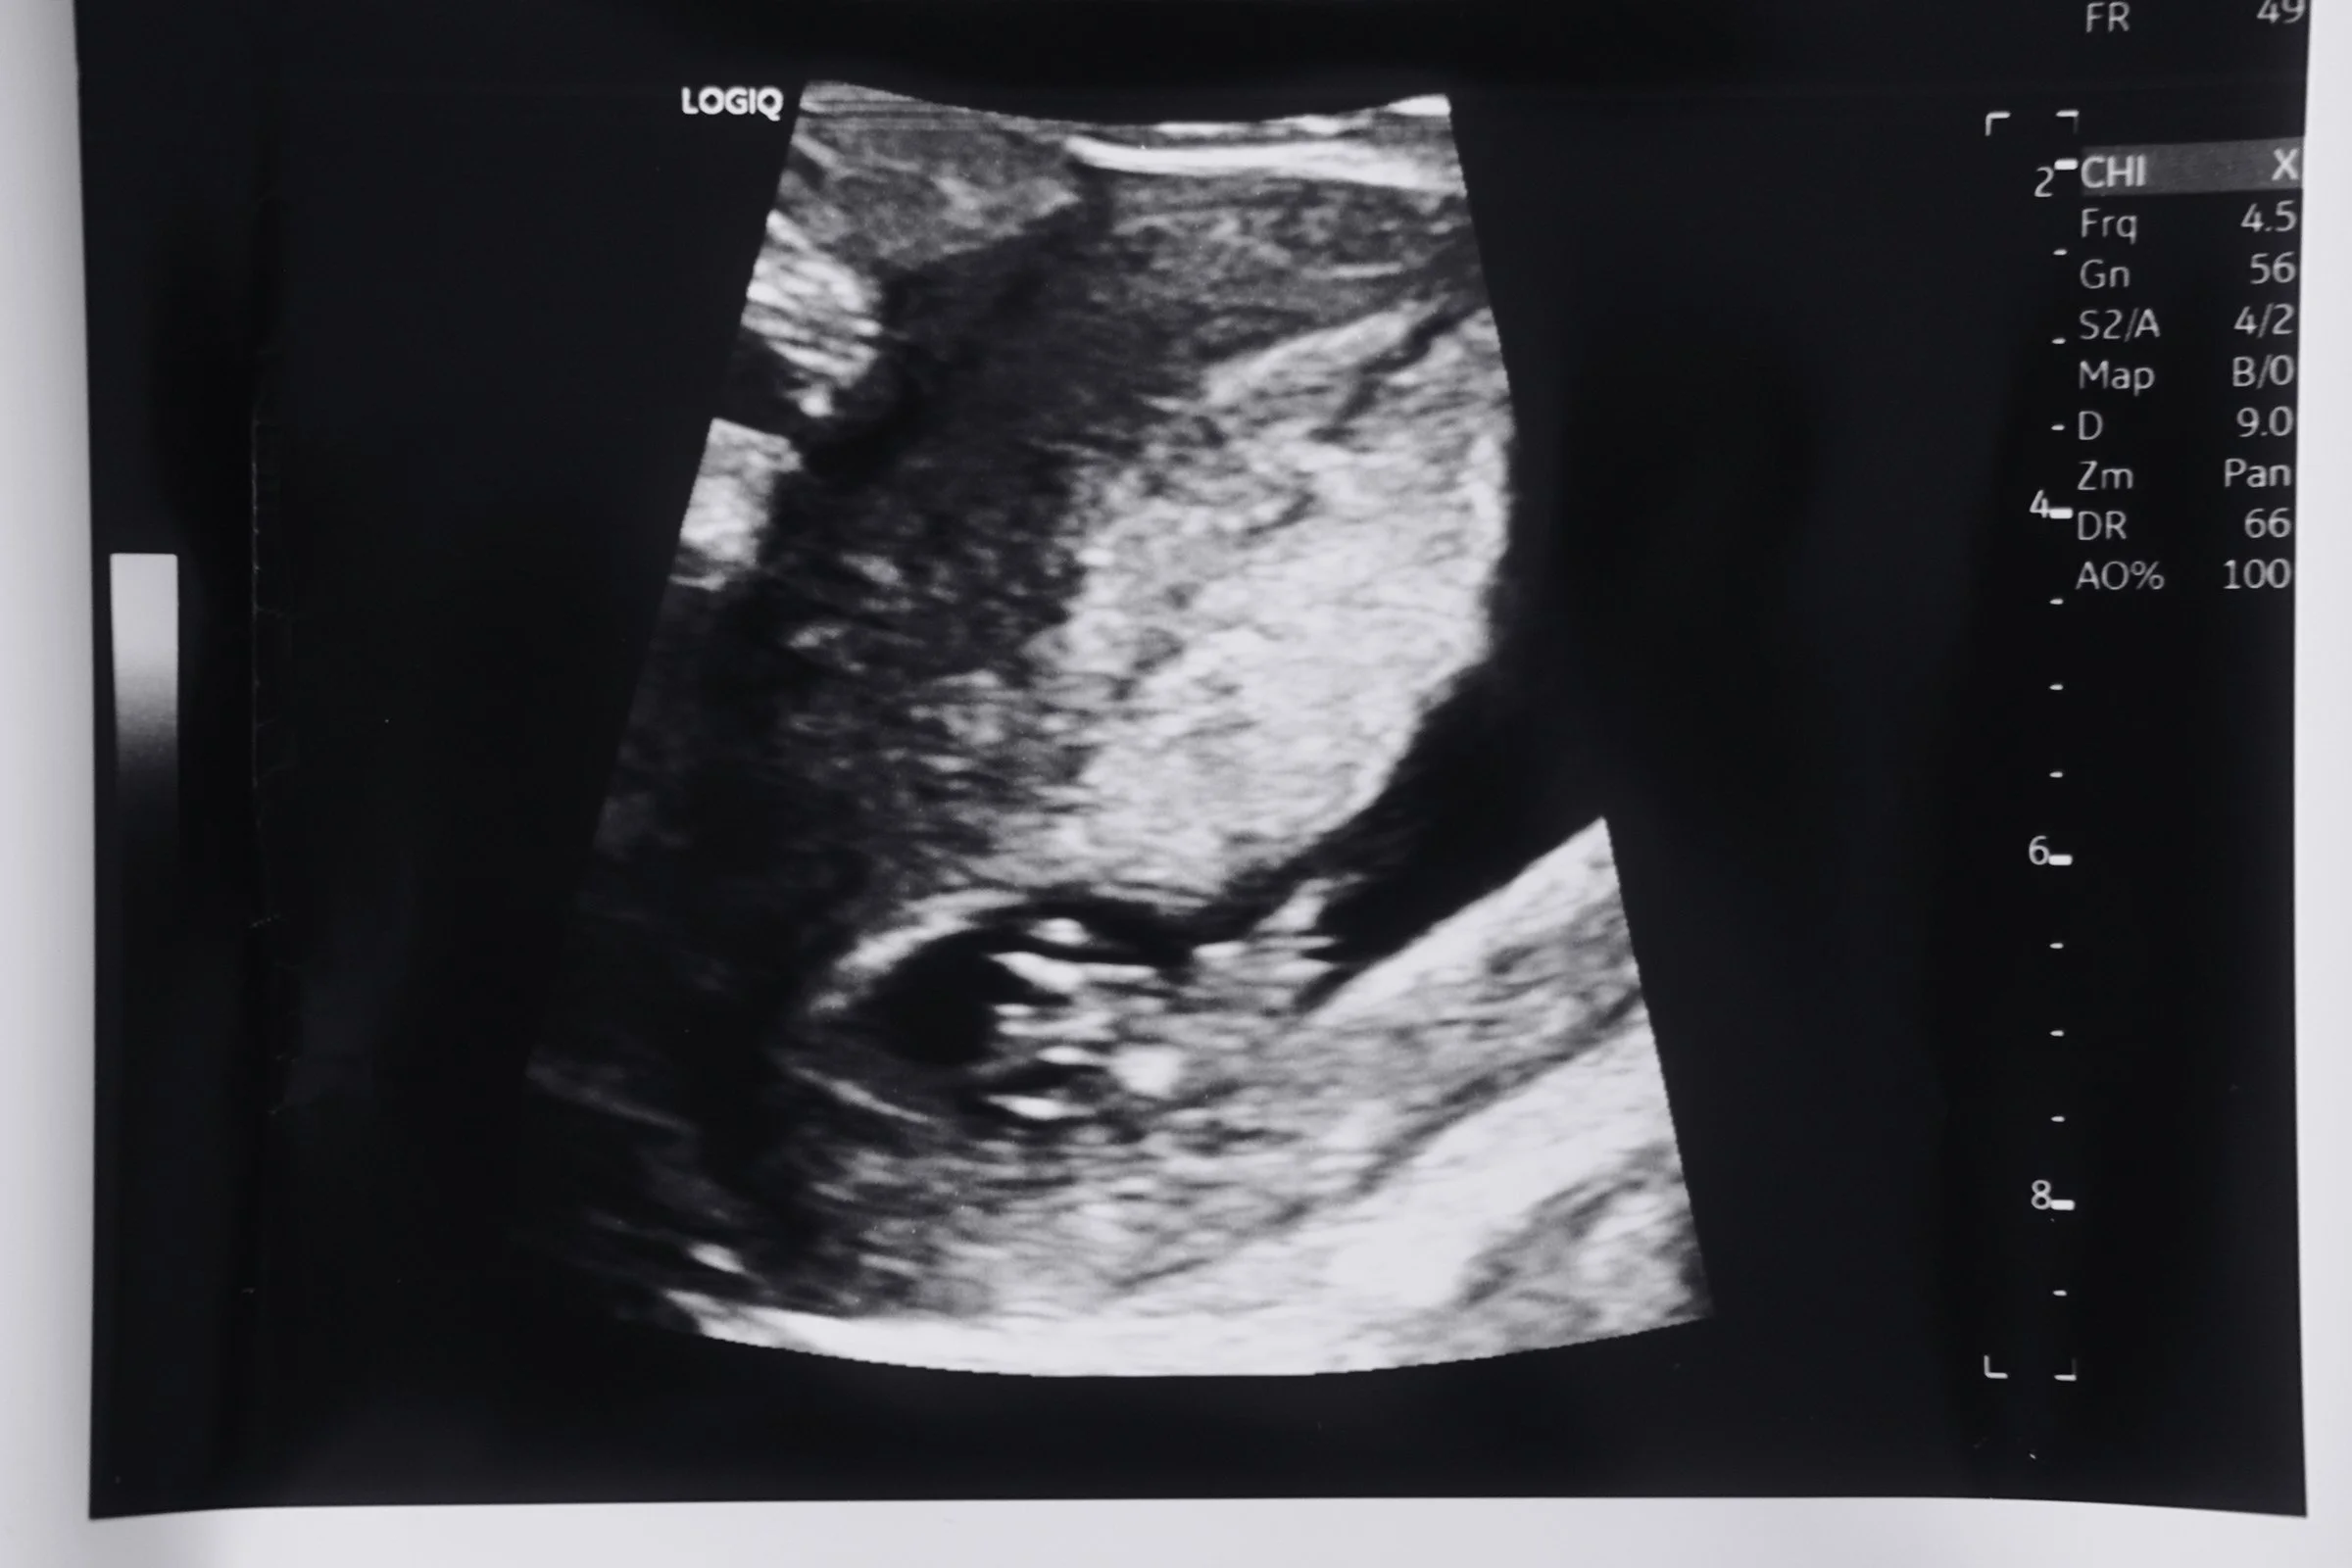

Oh - and perhaps starting the biggest adventure yet - finding out we’re pregnant! The true highlight this season has been the first trimester and the rollercoaster of experiences that comes with it. Baby Winty due November!

8 week dating scan!